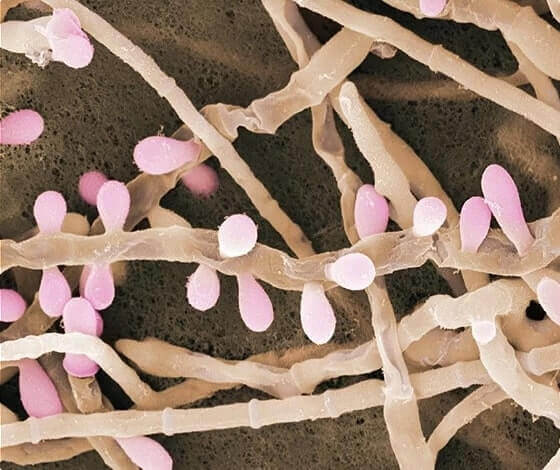

Достатъчно е едно докосване, за да хванете гъбичната инфекция, която поразява вашата кожа и нокти!

Заразяване с гъбична инфекция винаги протича

по един начин:

Ако навреме не се вземат нужните действия, гъбичките бързо започват да се разпространяват на участъци от кожата, засягайки при това косата, нокътите и дори вътрешните органи.